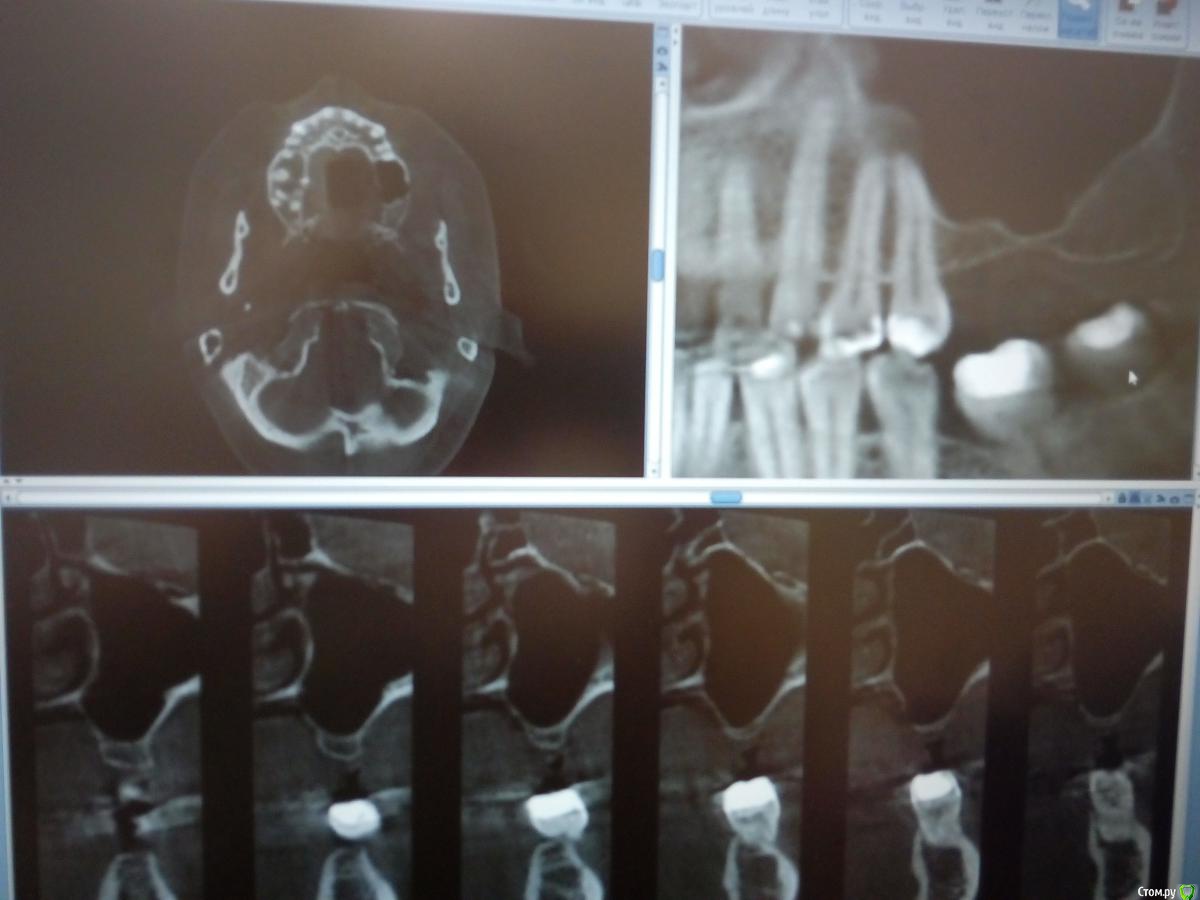

kamranchick Опубликовано 30 января, 2018 Поделиться Опубликовано 30 января, 2018 Господа приветствую, а можно ли как то оценить операцию синуса до сверления?Хорошо был произведен или нет? сделал с 2 сторон , но во 2 сегменте какая то странная ситуация.повторное кт через 6 месяцев. Ссылка на комментарий

red_butler Опубликовано 31 января, 2018 Поделиться Опубликовано 31 января, 2018 С обеих сторон странно выглядит Ссылка на комментарий

Борис80 Опубликовано 2 февраля, 2018 Поделиться Опубликовано 2 февраля, 2018 слева , видимо, десна вросла в окно, я бы предположил...На вскидку скажу, что на каждую пазуху минимум 2 грамма планирую, тем более когда там только кортикалка, Вы плотно "пакуете" материал ? Я бы сверлился и смотрел плотность Ссылка на комментарий

kamranchick Опубликовано 2 февраля, 2018 Поделиться Опубликовано 2 февраля, 2018 слева , видимо, десна вросла в окно, я бы предположил...На вскидку скажу, что на каждую пазуху минимум 2 грамма планирую, тем более когда там только кортикалка, Вы плотно "пакуете" материал ? Я бы сверлился и смотрел плотность торк 40 на каждой стороне, все хорошо получилось, но в 2 сегменте какая то кость непонятная вот как определять без сверления че и как, нигде и не описано Ссылка на комментарий

Борис80 Опубликовано 3 февраля, 2018 Поделиться Опубликовано 3 февраля, 2018 на кт имплантов нет, но они установлены? торк 40 где получился? Если уже установлены импланты, то теперь ждите ойтеста) Ссылка на комментарий

kamranchick Опубликовано 3 февраля, 2018 Поделиться Опубликовано 3 февраля, 2018 на кт имплантов нет, но они установлены? торк 40 где получился? Если уже установлены импланты, то теперь ждите ойтеста)отправил на 7 месяцев погулять)) торк 40 везде получился. скину через пару дней панорамку Ссылка на комментарий